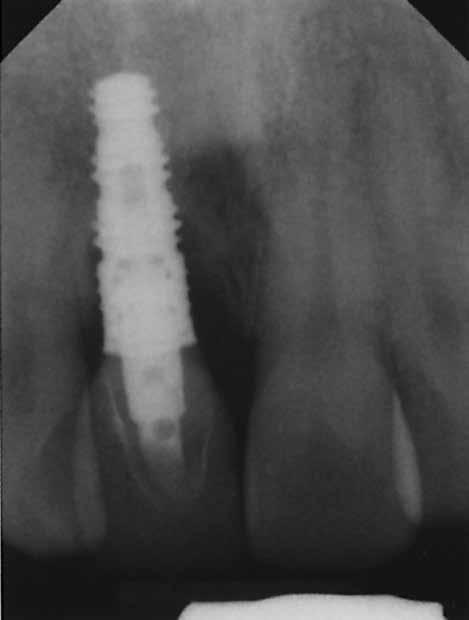

2. e. ábra: Kerámiafejre (Cerabase; Dentsply Sirona) készített végleges korona. 2. f ábra: A végleges korona átadásakor készített kontroll röntgenfelvételen látható, hogy a kresztális csont regenerációja nem megfelelő.

2. l ábra: Az egyéves kontroll röntgenfelvételen az augmentált terület regenerációja látható.

2. n ábra: Radiológiailag változatlan csontszint az augmentált csontszinthez képest, 20 évvel a protetikai rehabilitáció után.